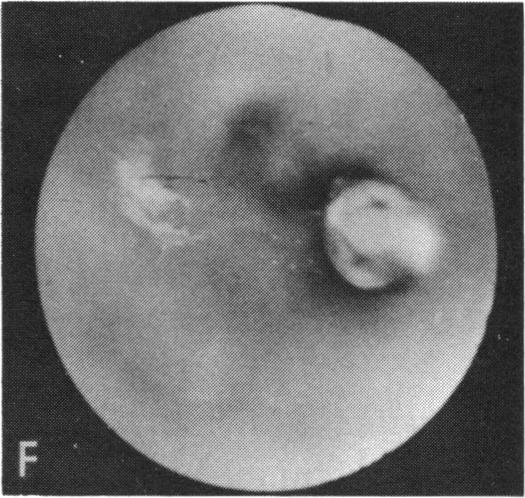

Coats' disease and congenital vascular retinopathy.

Trans Am Ophthalmol Soc. 1976;74:365-424.